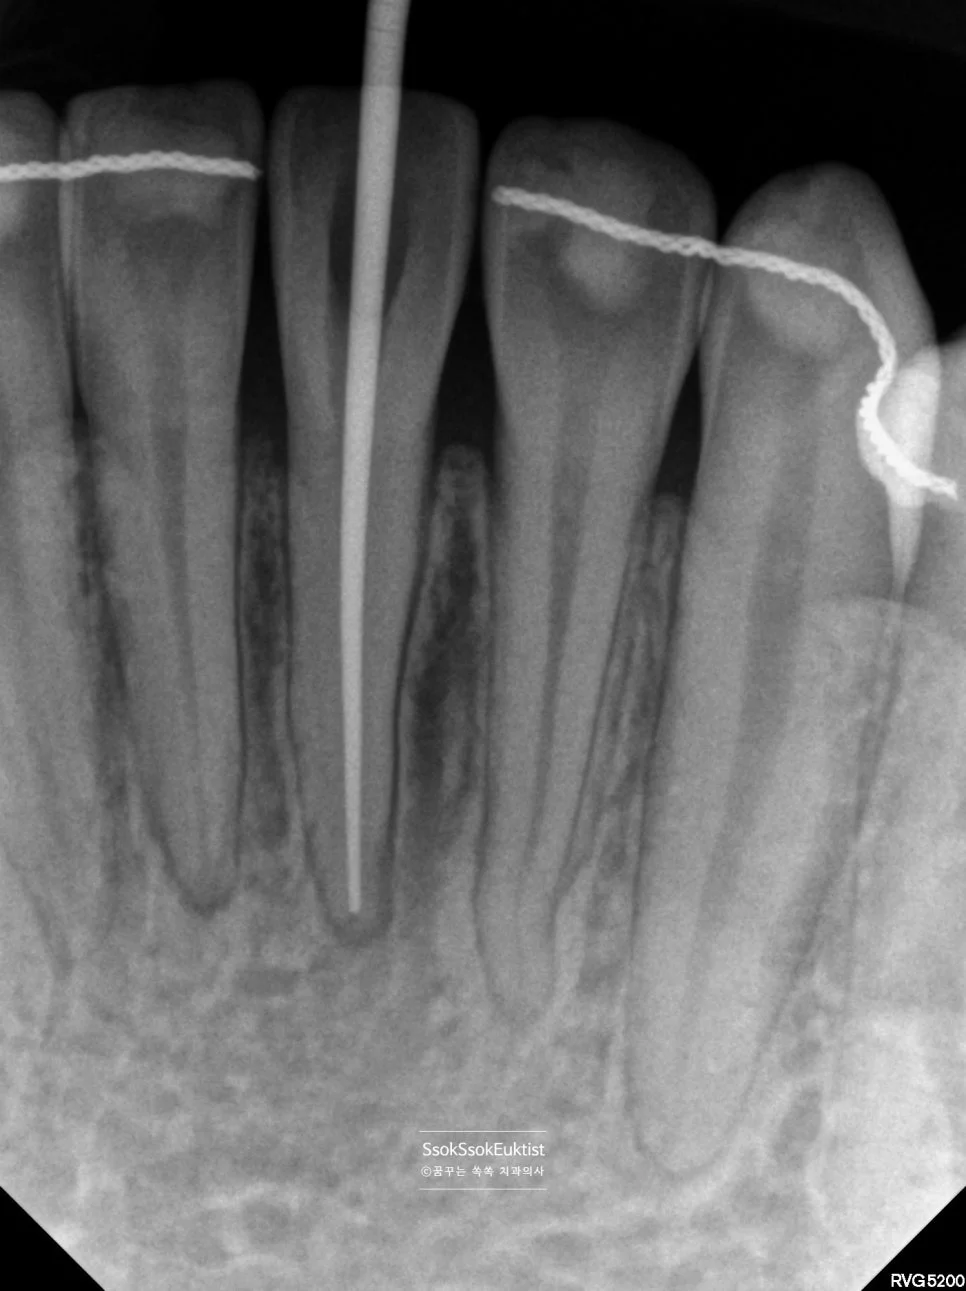

근관장 측정 X-ray — 신경관 끝까지 파일이 도달한 모습

통증이 있고 오랫동안 자극을 받은 치아이기에 당일 신경치료를 마무리하진 않습니다.

두 번째 내원일에 시린 느낌과 통증이 없었다는 것을 확인 후 신경치료 마무리 및 실활치 미백을 동시에 진행합니다.